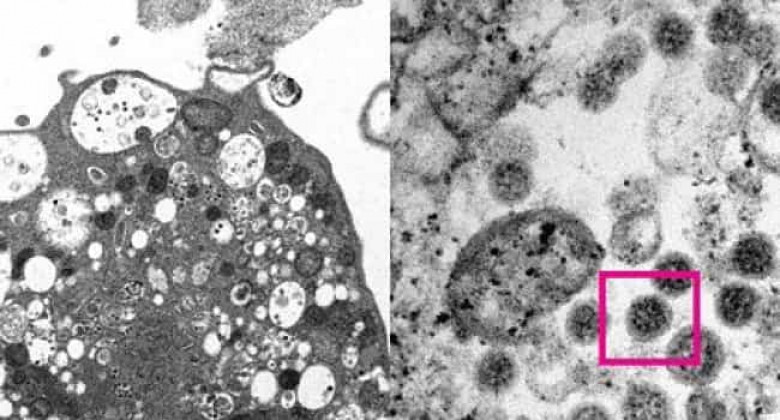

Ученые сфотографировали омикрон-штамм коронавируса

Ученым из Университета Гонконга впервые удалось сфотографировать омикрон-штамм коронавируса. Об этом рассказывается на сайте научного учреждения.

Исследователи сделали электронную микрофотографию клетки (Vero E6) почки обезьяны, инфицированной коронавирусом омикрон-штамма. На ней они увидели повреждения с набухшими везикулами, содержащими вирусные частицы.

При сильном увеличении ученым удалось разглядеть скопления характерных сферообразных объектов с шипами в форме короны на их поверхности.